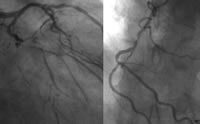

患者,65岁,男性,临床诊断扩张型心肌病。经序贯性诊断程序诊断为缺血性心肌病(图1~3),最终建议进行外科CABG或心脏移植手术治疗。

图3 CA示LAD、RCA中远段闭塞, 百拇医药